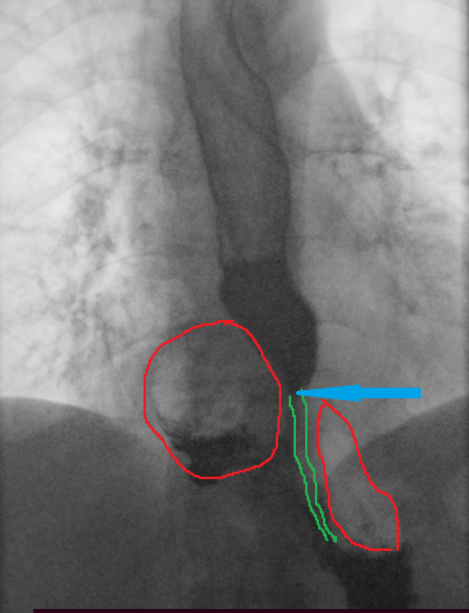

Gastroscopy. Green arrows: orifice of the gastrocolic fistula (Courtesy Dr. V. Penopoulos)